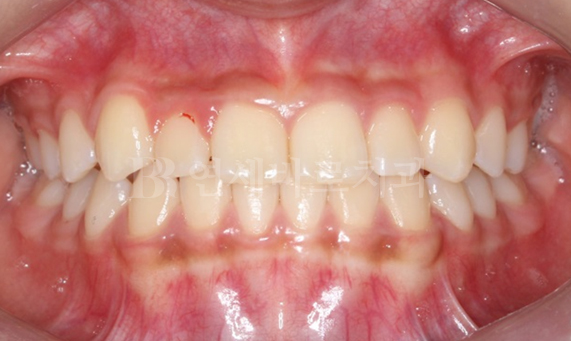

돌출입 교정 CASE

-